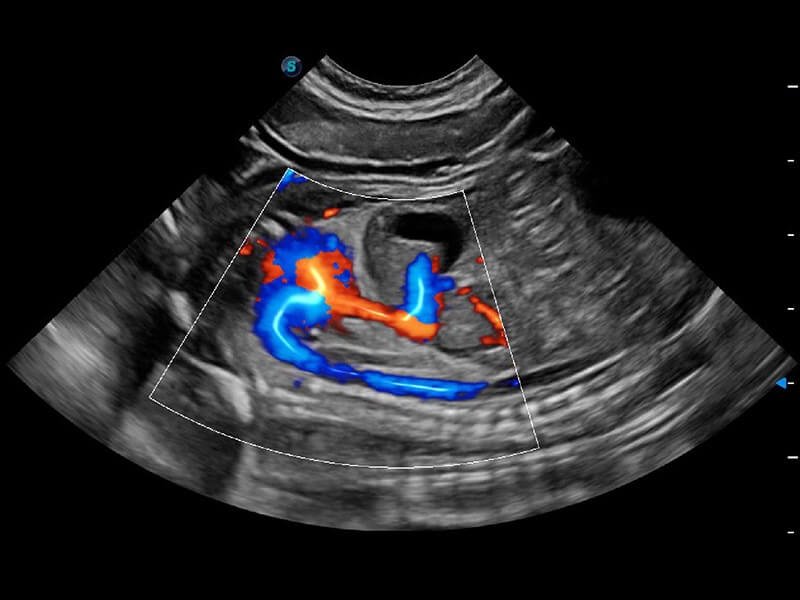

ProPet 60 作为一款高端台式动物超声设备,为动物医生的日常诊断提供了一系列贴合动物临床需求、解决临床实际问题的高级成像功能。凭借全系列高清探头,满足医生对腹部、心脏、生殖、浅表、肌骨等成像的所有需求,切实帮助您提升检查效率,提高诊断信心。